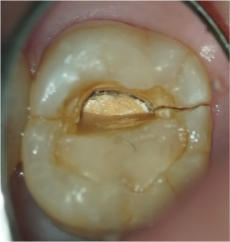

歯根破折の確認

歯根破折の確認歯の内部から確認する

歯根が割れているかどうかはレントゲンやCTでも判別できないことがあります。マイクロスコープで歯の内部から割れ目がないか精査します。